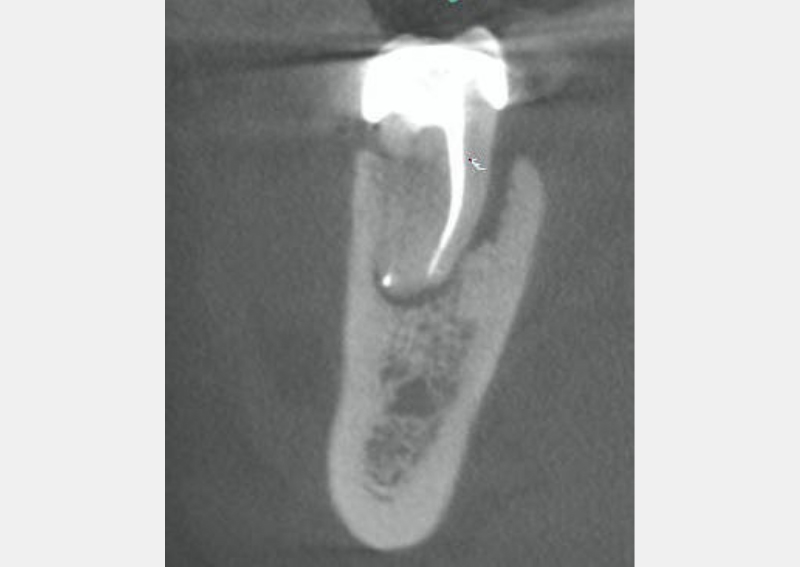

This is known as “fracture necrosis.” Figures 1A-1C highlight an undiagnosed root fracture in the lower second molar. Note non-vital pulp with periapical/periradicular bone loss and no restoration or caries. The clinician should question why the pulp became non-vital. With no other objective etiology, a vertical root fracture should be considered.

Radiographs and especially CBCT are valuable diagnostic tools for determining the presence of a root fracture. Unfortunately, unless the fracture is wider than about 0.15 mm (the tip of a #15 endodontic file), it cannot be visualized in the CBCT scan. There are some strong associations between radiographic findings and the presence of a root fracture. Specifically, when the bone loss presents in a “J” shaped pattern, it is highly suggestive that a root fracture is present.

This can often be seen on a two-dimensional periapical radiograph, with the bony lesion typically extending from the apex to the crestal bone, sometimes resulting in a deep and narrow isolated periodontal pocket. This pocket sometimes cannot be probed because it occurs in the interproximal area. Taking radiographs of the lower second molars can be challenging, especially with patient compliance (sometimes the tooth is “way back there” and may be uncomfortable for the patient).

Consider this: lower second molars are typically positioned in the cancellous bone, almost directly in the middle of the buccal and lingual cortical bony plates. When pulp necrosis becomes infected, the subsequent bone loss is only observed on a periapical radiograph when the bone loss reaches the junction of the cancellous and cortical bone. This makes the radiographic diagnosis of pulp necrosis difficult, especially for the lower second molar. CBCT can be essential in determining periapical or periradicular bone loss (see Figures 2A-2B).